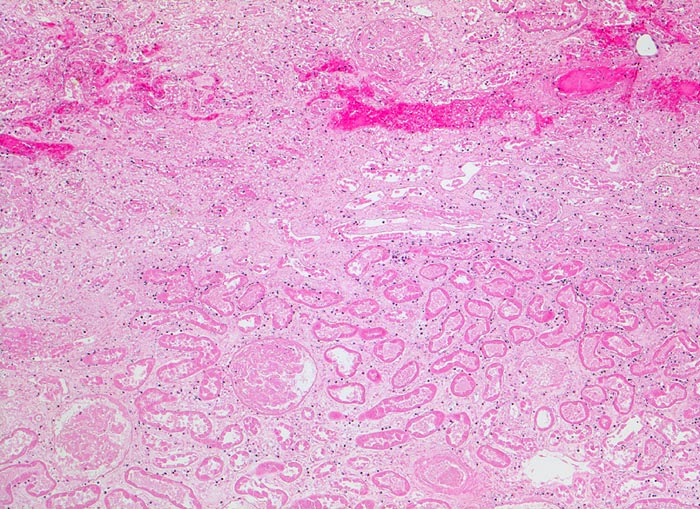

Akute Infarkte bilden histologisch scharf begrenzte kokardenförmig aufgebaute Herde mit zentraler Koagulationsnekrose umgeben von einem Saum neutrophiler Granulozyten. In der Peripherie ist das partiell geschädigte Gewebe ödematös hämorrhagisch und enthält dilatierte hyperämische Gefässe. Die Nekrose wird durch neutrophile Granulozyten und Makrophagen abgebaut und durch Granulationsgewebe ersetzt, welches zu einer gefässarmen Narbe schrumpft. Die äusserste Rindenzone bleibt infolge der Kollateralversorgung durch Kapselgefässe oft vom Infarkt ausgespart. Infarktnarben können wie alle Narben verkalken.